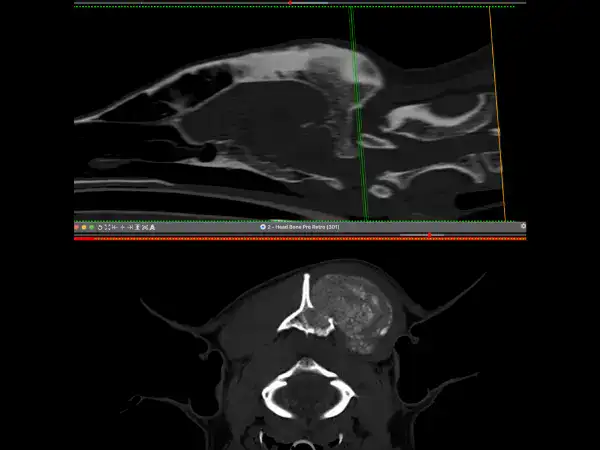

Beau, a 7-year-old male neutered German Shepherd, was referred to us in June 2025 for investigation and treatment of a slow-growing mass on the back of his skull.

CT confirmed an osteoproliferative mass originating from the nuchal crest, the appearance of which was typical for multilobular tumour of bone, also known as a multilobular osteochondrosarcoma (MLO). The histopathological diagnosis of MLO was confirmed with a minimally invasive biopsy.